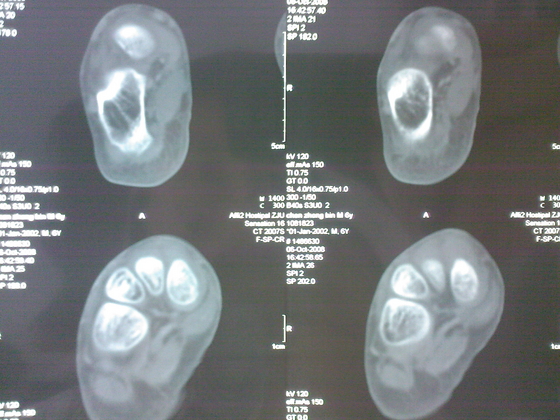

把病理送浙一医会诊后诊断为:骨外软骨瘤。同时做了CT检查。暂未予治疗。

今天把创面情况跟CT发上请大家看看。

继续发CT片